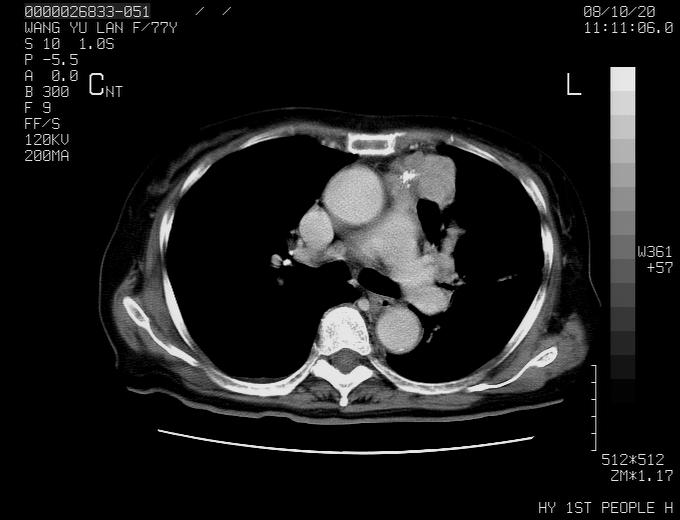

动脉期未见大血管同步强化,首先考虑周围型肺癌

动脉期病灶近中线侧可见星芒状与大血管同等强化密度,支持考虑血管畸形伴血栓形成,动脉期不曲型,不除外周围型肺癌

左肺周围型肺癌并肺门淋巴结转移,很典型了!